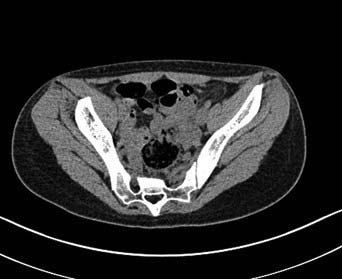

Больная 15 лет. Жалобы: на укорочение правой нижней конечности, хромоту.Анамнез: Со слов болеет с детства, травму отрицает. Ранее за медицинской помощью не обращалась. Последние 2 года отмечает резкое укорочение конечности. Локально: При осмотре отмечается умеренное искривление позвоночника во фронтальной плоскости, умеренная асимметрия лопаток и надплечий. Скошенность таза. Отмечается укорочение правой нижней конечности на 3 см. Движения в тазобедренном и коленном суставах в полном объеме. Нейрососудистых нарушений в периферических отделах нет.

Наверно целесообразно добавить,что болевого синдрома нет,движения в суставе в полном объёме.Я бы уточнил,что жалобы скорее косметического характера(асимметрия при ходьбе и западение вертельной области справа. Укорочение фигурировало как единственный диагноз в направлении на лечение к нам.Компенсация "укорочения" увеличением высоты каблука обуви не устраняет асимметрию таза и в статике и мало улучшает походку.Вопрос-стоит ли в конкретном случае идти на тройную остеотомию таза и латерализацию вертлужной впадины? Мне представляется,что не стоит.